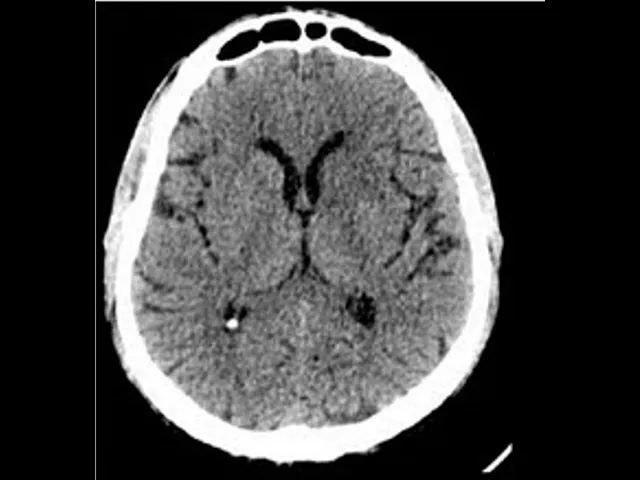

entre os tecidos na ressonância da vida a diferente proporção diferente quantidade dos átomos de hidrogênio é muito bem voltando a tomografia é um dos exames mais utilizados em neurologia e neurocirurgia é um exame de rápido aquisição de fácil interpretação um exame que não tem o custo tão elevado quanto o da ressonância e que resolve grande parte dos problemas sobretudo é urgência neurológico a analisar uma tomografia e aqui nós temos nessa foto um corte axial de uma tomografia é normal eu preciso entender que a variável a grandeza que esse exame tomografia me fornece é a densidade

dos tecidos bom então os raios-x emitidos pelo aparelho de tomografia vão atravessar os tecidos esses eram atenuados a dependendo da densidade de cada tecido oi e o computador vai interpretar é só atenuação diferencial nos mais diferentes os tecidos atravessados pela radiação e faz um fornecer uma imagem reconstituído então veja que quanto mais densa uma estrutura é mais branca ela vai aparecer no exame então veja que a calota craniana é bastante densa e aparece branca luiza é o ar que está aqui dentro dos seios paranasais aqui o seio frontal muito pouco de sua estrutura menos densa

que aparece bastante escuro preto o líquido veja líquido aqui no interior do ventrículo também nas fissuras e vai aparecer também nessa externas também pouco denso é preto e o cérebro e em tons variados de cinza a depender da maior ou menor densidade é sempre importante que eu perceba a centralização da linha média a existência de sulcos e giros a diferenciação entre a substância branca ea substância cinzenta que aparecem até invertidos os nomes branco e cinzento na tomografia por conta da densidade e assim que se analisa de início uma tomografia do crânio é importante examinar os

vários cortes e nas incidências axial como é o caso desse corte mas também na incidência sagital e na incidência coronal e vamos comparar com essa outra tomografia que traz uma série de alterações veja ventrículos dilatados e na parte cerebral eu já vejo mais dificuldade em identificar sulcos e giros eu recebi mais dificuldade em fazer a diferenciação entre as substâncias branca e cinzenta e eu tenho aqui um sinal importante veja o cursor uma área que é a escura mas não tanto quanto o interior do ventrículo isso aqui representa líquido sendo forçado para fora do ventrículo por

hipertensão na direção do parênquima é um sinal chamado o transformação transependimario posso ver aqui ó o curso ou bom então caso de uma paciente com hidrocefalia com hipertensão intracraniana é um dos vários exemplos que nós vamos mostrar e o que você vê que é possível analisar um quadro de doença um quadro patológico com o exame de neuroimagem eu vejo agora a mesma doença e você família estudada pela ressonância magnética ressonância da muito mais detalhe do que a tomografia então veja ventrículos dilatados aumentar es a brisa de sulcos e giros dificuldade de diferenciação entre as substâncias